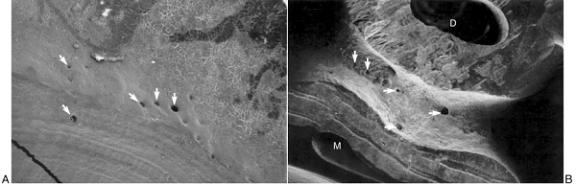

In urma observatiilor facute la microscopul electronic, diametrul canalelor furcale a molarilor mandibulari variaza de la 4 pana la 720m.

Figura 6. Aspect la microscopul electronic a canalelor furcale

Numarul lor variaza de la nici unul pana la 20 per dinte. Foramine atat pe podeaua camerei pulpare cat si-n furcatie au fost descoperite la 36% din molarii 1 superiori, 12% molarii 2 superiori, 32% la molarii 1 inferiori si 24% la molarii 2 inferiori. Dintii inferiori prezinta o incidenta mai mare a numarului de numarului de foramine ce implica atat camera pulpara cat si furcatia (56%) fata de dintii superiori (48%). Radiografiile nu au reusit sa demonstreze prezenta canalelor furcale si a celor laterale din treimea coronara a acestor radacini.